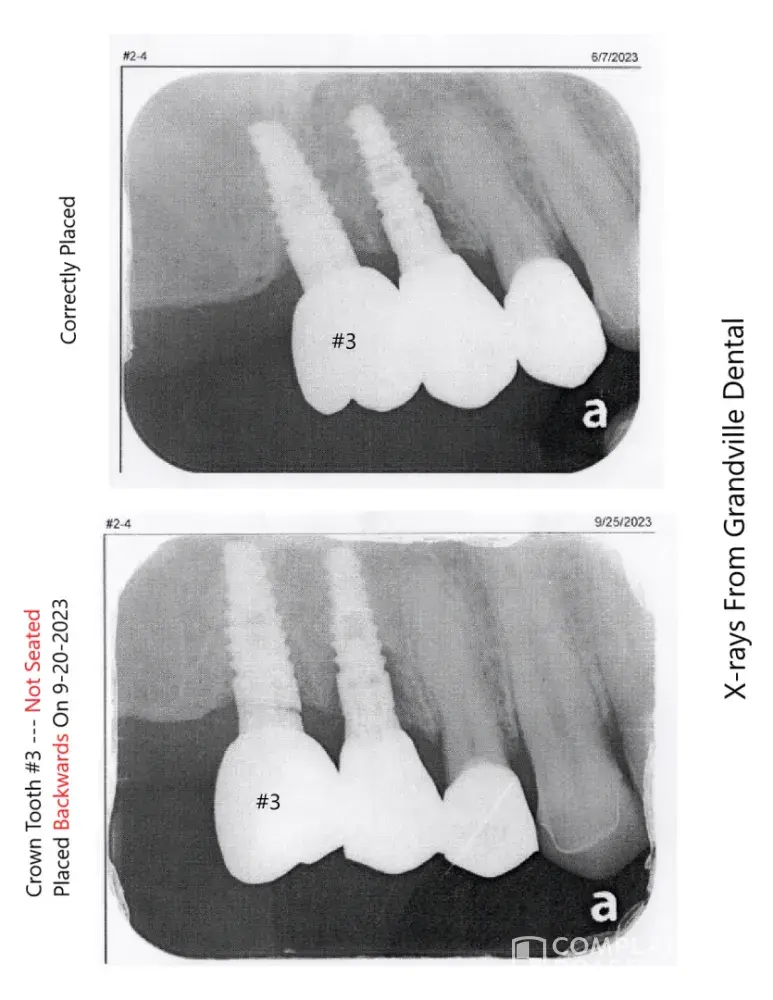

Grandville Dental Health Center PC - Full mouth restoration - dental crowns & bridges

I've spent over $50,000 on a full mouth restoration through Grandville Dental Health Center plus another $4,000 figuring out issues and it took over a year but I found out they messed up by placing a crown 180 degrees backwards and wrecked my full restoration then abandon me for no reason because they couldn't figure it out. Permanent adjustments were made...